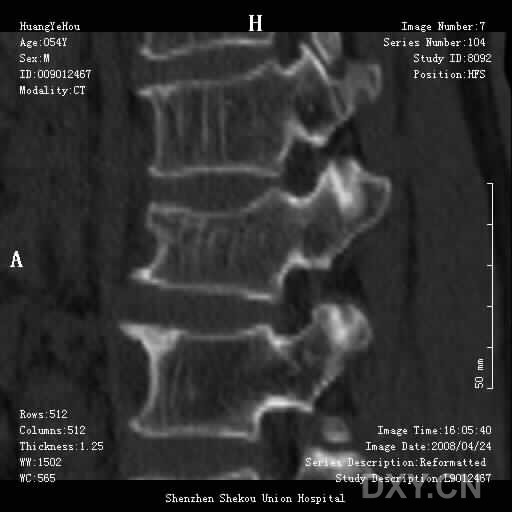

男,54岁,腰部外伤疼痛2小时!

1、腰3椎体压缩骨折

2、腰椎退行性变。

这么好的片子没见过 不知l2,l3椎板是否有问题 ,好象有线样低密度影

1.腰椎椎体压缩性骨折,  2. 退行性改变(局限性骨质密度增高.

目前可以考虑  压缩骨折,椎体退变。请出示原始周围扫描图像

前缘变窄;压缩骨折;椎体硬化征;退行性变